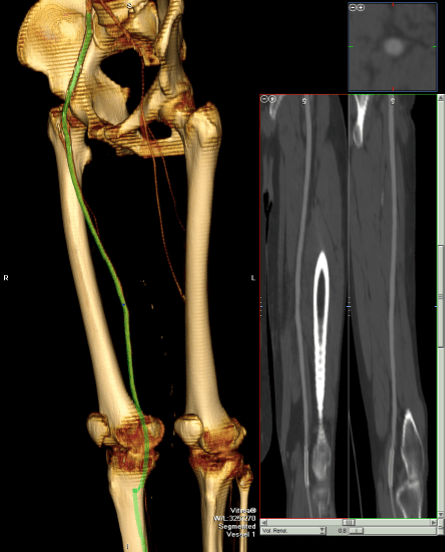

The patient came back in followup -it has been 4 years since his infection was repaired. He was complaining of short distance claudication. His wound healed well and remains closed. CTA shows along with his short segment SFA occlusion which we will treat, a widely patent R. EIA (below).

The remote endarterectomy of the external iliac artery remains patent. Compare this to the preop CTA which I found and wasn’t available when I posted this case originally:

The chronically occluded EIA can be readily seen. The artery shown in the current CTA is that recanalized artery.

CTA (pictured above and below) showed a 5.1cm infrarenal AAA with an hourglass shaped neck with moderate atherosclerosis in the neck, an occluded left common iliac artery with external iliac artery reconstitution via internal iliac artery collaterals, and a right external iliac artery occlusion with common femoral artery reconstitution. There was calcified right common femoral artery plaque.